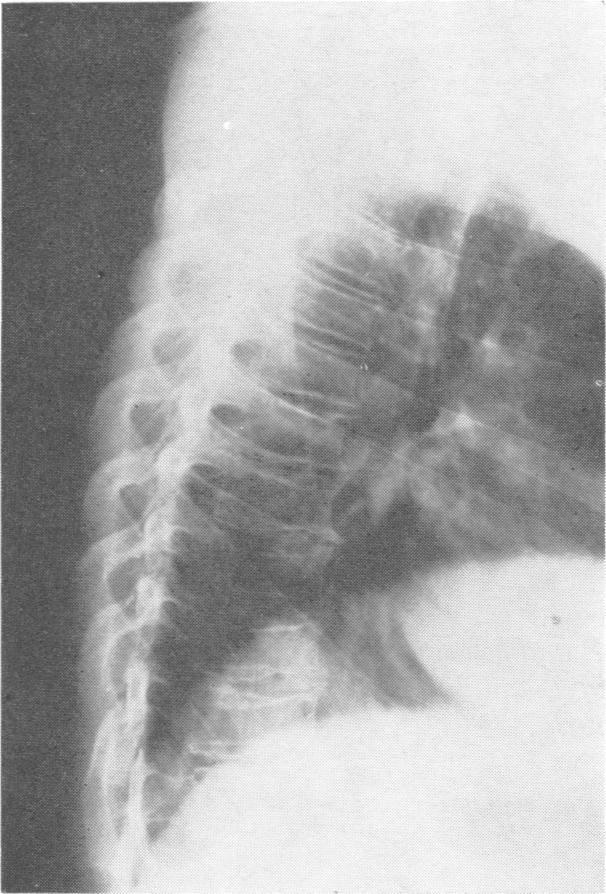

Two first cousins with spondyloepiphyseal dysplasia tarda (X linked recessive form), one also with poikiloderma atrophicans vasculare progressing to lymphocytic lymphoma.

Two male cousins with spondyloepiphyseal dysplasia tarda (X linked recessive form) are described. One presented with a poorly differentiated lymphocytic lymphoma of the skin in areas of poikiloderma atrophicans vasculare which had been present for 10 years.